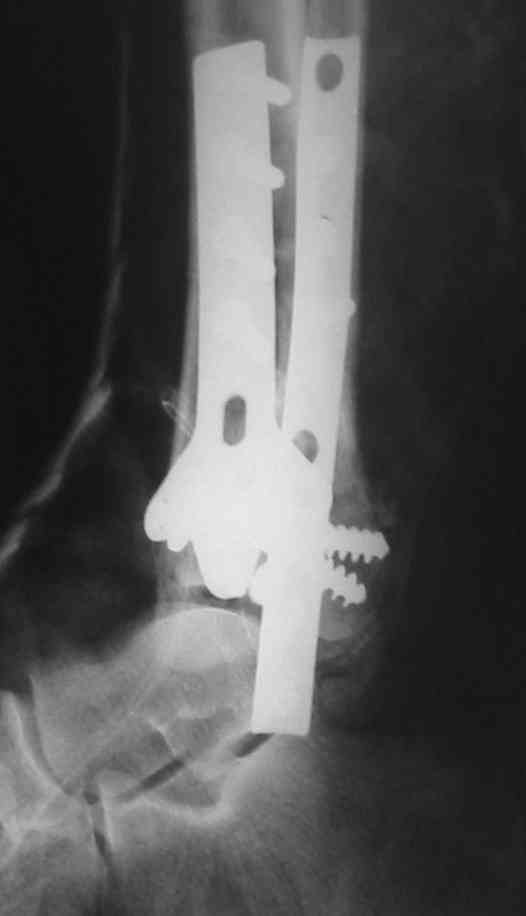

OK, Dr Driagin, Ja operiroval bolnogo po Vashemu, hotia sam ni ochen' ubezden' v itom, t.k. bolnoi otkazalsa na proch' ot ex.fix, ja emu sdelal ORIF + Kostnia plastika, snimky prelogiottsa,

Очень прилично получилось, но мне показалось, что винты на 4,5 мм.Это принципиально винты используются 3,5 и 4,0 мм. И проекцию прямую бы переделать. С уважением Дрягин

Пластина лист клевера есть в варианте DCP -динамическая компрессирующая пластина.В ней все отверстия круглые,развальцованные отверстия под винт 3,5, чтобы шляпка винта не торчала.Винты 4,5 тоже проходят в эти отверстия, но шляпка не погружается.Могут быть проблемы с мягкими тканями.Пластина LCP -пластина с блокированием.В каждом отверстие пластины нарезана резьба и на шляпке винта такая же.Получается блок винт-пластина-кость.Очень крепко.Первоначально она готовилась для остеопороза, много лет в Давосе её разрабатывали.Я видел там первые образцы ещё в 1995 году, а начали они в 80-годах.Насчёт оси по рентгенограмме пока не согласен пусть сделают хорошую, правильную прямую проекцию.С уважением Дрягин

Мне кажется, что все конечно далеко от идеала. Сложный перелом. Есть ощущение, что малоберцовая кость (ключ!) фиксирована с ротацией и удлинением. Снимки конечно необходимо сделать в правильных проекциях и без гипса...

В голеностопном суставе обязательны 3 стандартные ренгенологические проекции: прямая, латеральная и мортиз. Без них невозможно трактовать состояние голеностопа.

Применение шурурпов 4.5 мм и более толстых пластин крайне недопустимы. Рекомендуется низкопрофильные, контурированные пластины с шурупами 3.5 мм, а иногда те же 3.5 шурупы но с головкой 2.7 мм.